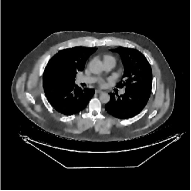

This section compares the reconstruction quality and runtime among the proposed MBIR method, PWLS-ST-, and other three MBIR methods, PWLS-EP, PWLS-DL, and PWLS-ST-. Table I shows that, for both 2D and 3D sparse-view CT reconstructions of the XCAT phantom, the proposed PWLS-ST- model outperforms PWLS-EP and PWLS-ST- in terms of RMSE. In addition, PWLS-ST- using a square transform (of size ) achieves lower RMSE than PWLS-DL using an overcomplete dictionary (of size ) for 2D sparse-view reconstructions. Fig. 3(a) and Fig. 4 show the reconstructed images for 2D and 3D phantom experiments, with different reconstruction models and different number of views. (See the corresponding error maps in the supplement.) The proposed PWLS-ST- consistently gives more accurate image reconstructions compared to other MBIR methods. Specifically, PWLS-ST- has smaller errors in the heart region (see zoom-ins in Fig. 3(a)) of 2D reconstructions than PWLS-DL and PWLS-ST-. In addition, compared to PWLS-ST-, PWLS-DL and PWLS-ST- have some ringing artifacts around the edges with high transition, e.g., edges between air and soft tissues. (See a comparison of profiles of PWLS-ST- and PWLS-ST- in the supplement.) In particular, PWLS-ST- and PWLS-DL give more visible ringing artifacts for 2D reconstruction from fewer views, and PWLS-ST- has these ringing artifacts for 3D reconstructions regardless of the number of views (see zoom-ins in Fig. 4). Table II reports runtimes of different MBIR methods in reconstructing the -views XCAT phantom scan. (FBPConvNet is a non-MBIR method and its runtime for processing a image is approximately one second with a TITAN Xp GPU.) While providing better reconstruction quality, the proposed Algorithm 1 of PWLS-ST- has shorter runtime compared to the algorithms of PWLS-DL and PWLS-ST- in Section III-A. Similar to the PWLS-EP algorithm, the reconstruction time of the PWLS-DL, PWLS-ST-, and PWLS-ST- algorithms can be further reduced by using ordered subsets [51].

![]() |

| (a) 2D fan-beam CT experiments |

Fig. S.6 shows the error images (corresponding to Fig. 3(a)) of 2D reconstructions with the PWLS-EP, PWLS-DL, PWLS-ST-, and PWLS-ST- methods. The proposed PWLS-ST- approach consistently provides more accurate reconstructions compared to the other methods. Specifically, PWLS-ST- has smaller errors in the heart region (see zoom-ins) of 2D reconstructions than PWLS-ST- and PWLS-DL. In addition, PWLS-ST- does not have ringing artifacts around the edges with high transition. Compared to PWLS-ST-, PWLS-ST- and PWLS-DL give more and stronger ringing artifacts in reconstruction for views (see zoom-ins).